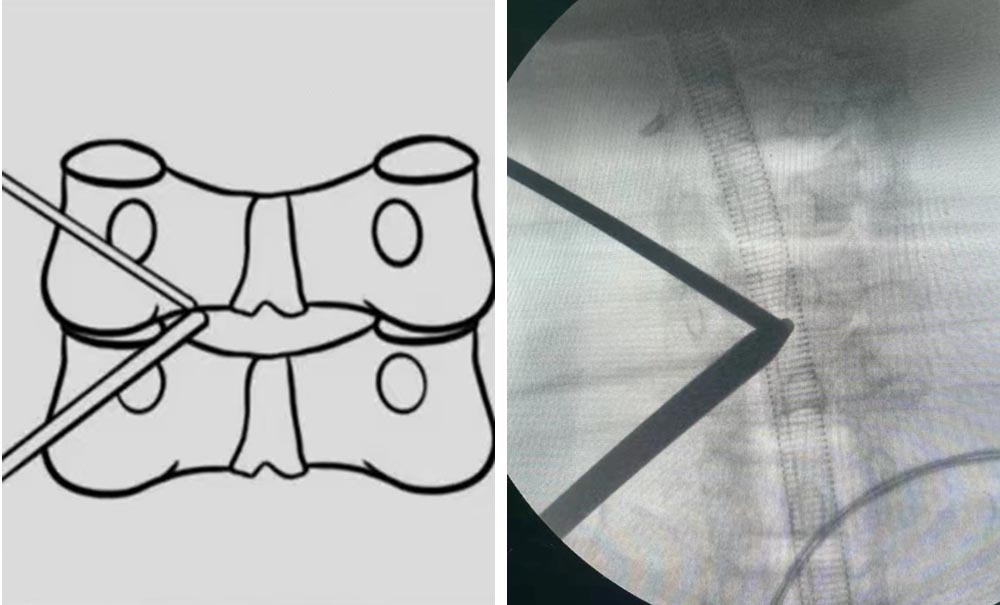

UBE技术是一种新兴的脊柱微创内镜技术。该技术只需做两个钥匙孔大小的切口,建立两个通道(一个视野通道,一个操作通道)进行操作。相较于单通道内镜技术,该技术具有镜下视野更全面,器械操作更灵活,器械选择更多等诸多优点,已应用于椎间盘突出髓核摘除,椎管或椎间孔狭窄的减压,椎管内囊肿、血肿、脓肿的清除,以及内镜辅助下椎体间融合,未来能使更多更复杂的脊柱退变性疾病实现微创化、内镜化治疗。

UBE技术示意图